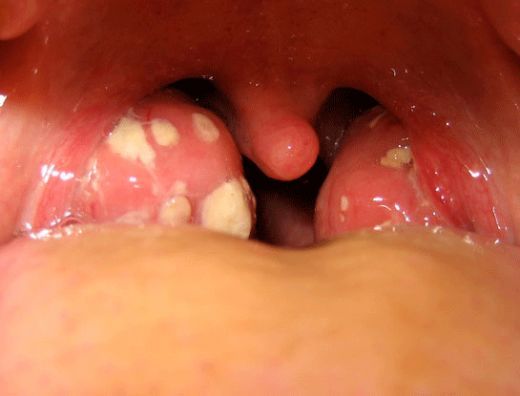

- Boğazda şişlik ve kızarıklık